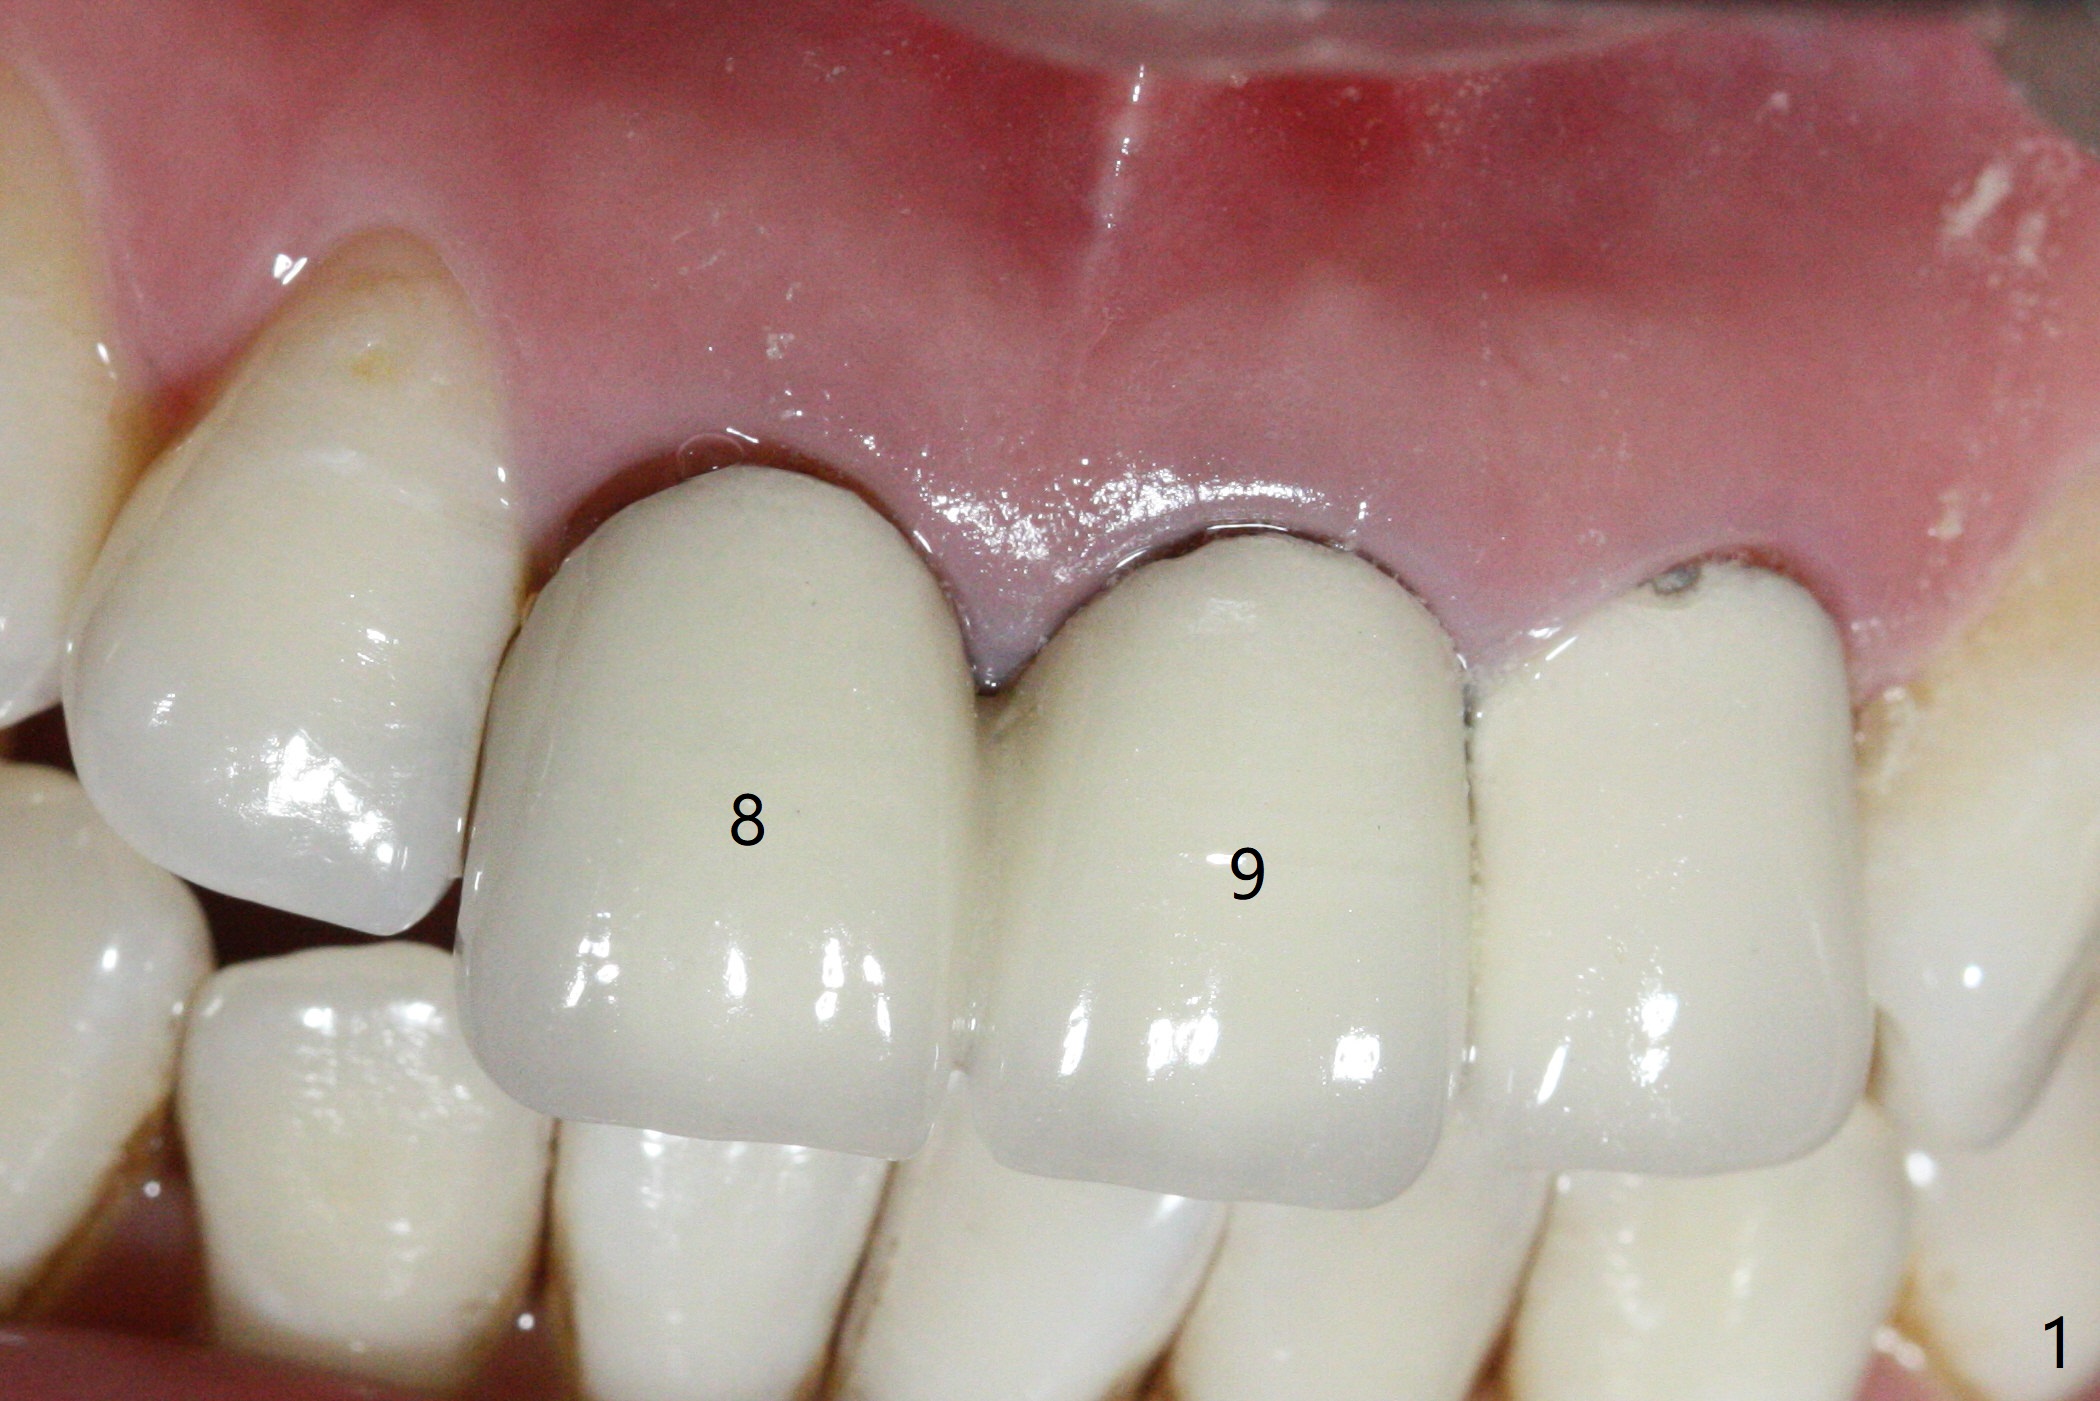

After sectioning the splinted crowns at #8 and 9 (Fig.1,2 (*: open bite)), the tooth #9 is deemed nonsalvageable because of caries and the crown/retainer of #8 is recemented. The trajectory of initial osteotomy is off (Fig.3 (red line: ideal trajectory)). Using Lindamann bur twice does not improve the trajectory (Fig.4,5). It appears that a new osteotomy should be established in the distal wall of the socket (Fig.5 red line (initial entry point and angle), Fig.6). Following sequential osteotomy, a 4x10 mm dummy implant is placed with stability and ~ 3.5 mm apical space (Fig.7 red line). A final implant (4x11.5 mm) is placed subcrestal (except buccal, Fig.8). With further placement of the implant, a 4.5x5.5(3) mm abutment and Vera graft are placed (Fig.9) prior to fabrication of an immediate provisional. In all, a new osteotomy site should be set up when the trajectory is to be changed substantially. There is no gross bone loss 4.5 months postop (Fig.10). There is shade mismatch when a porcelain-fused-Zirconia crown is tried in (Fig.11, as compared to Fig.1). The latter is corrected when a PFM crown is cemented (Fig.12).